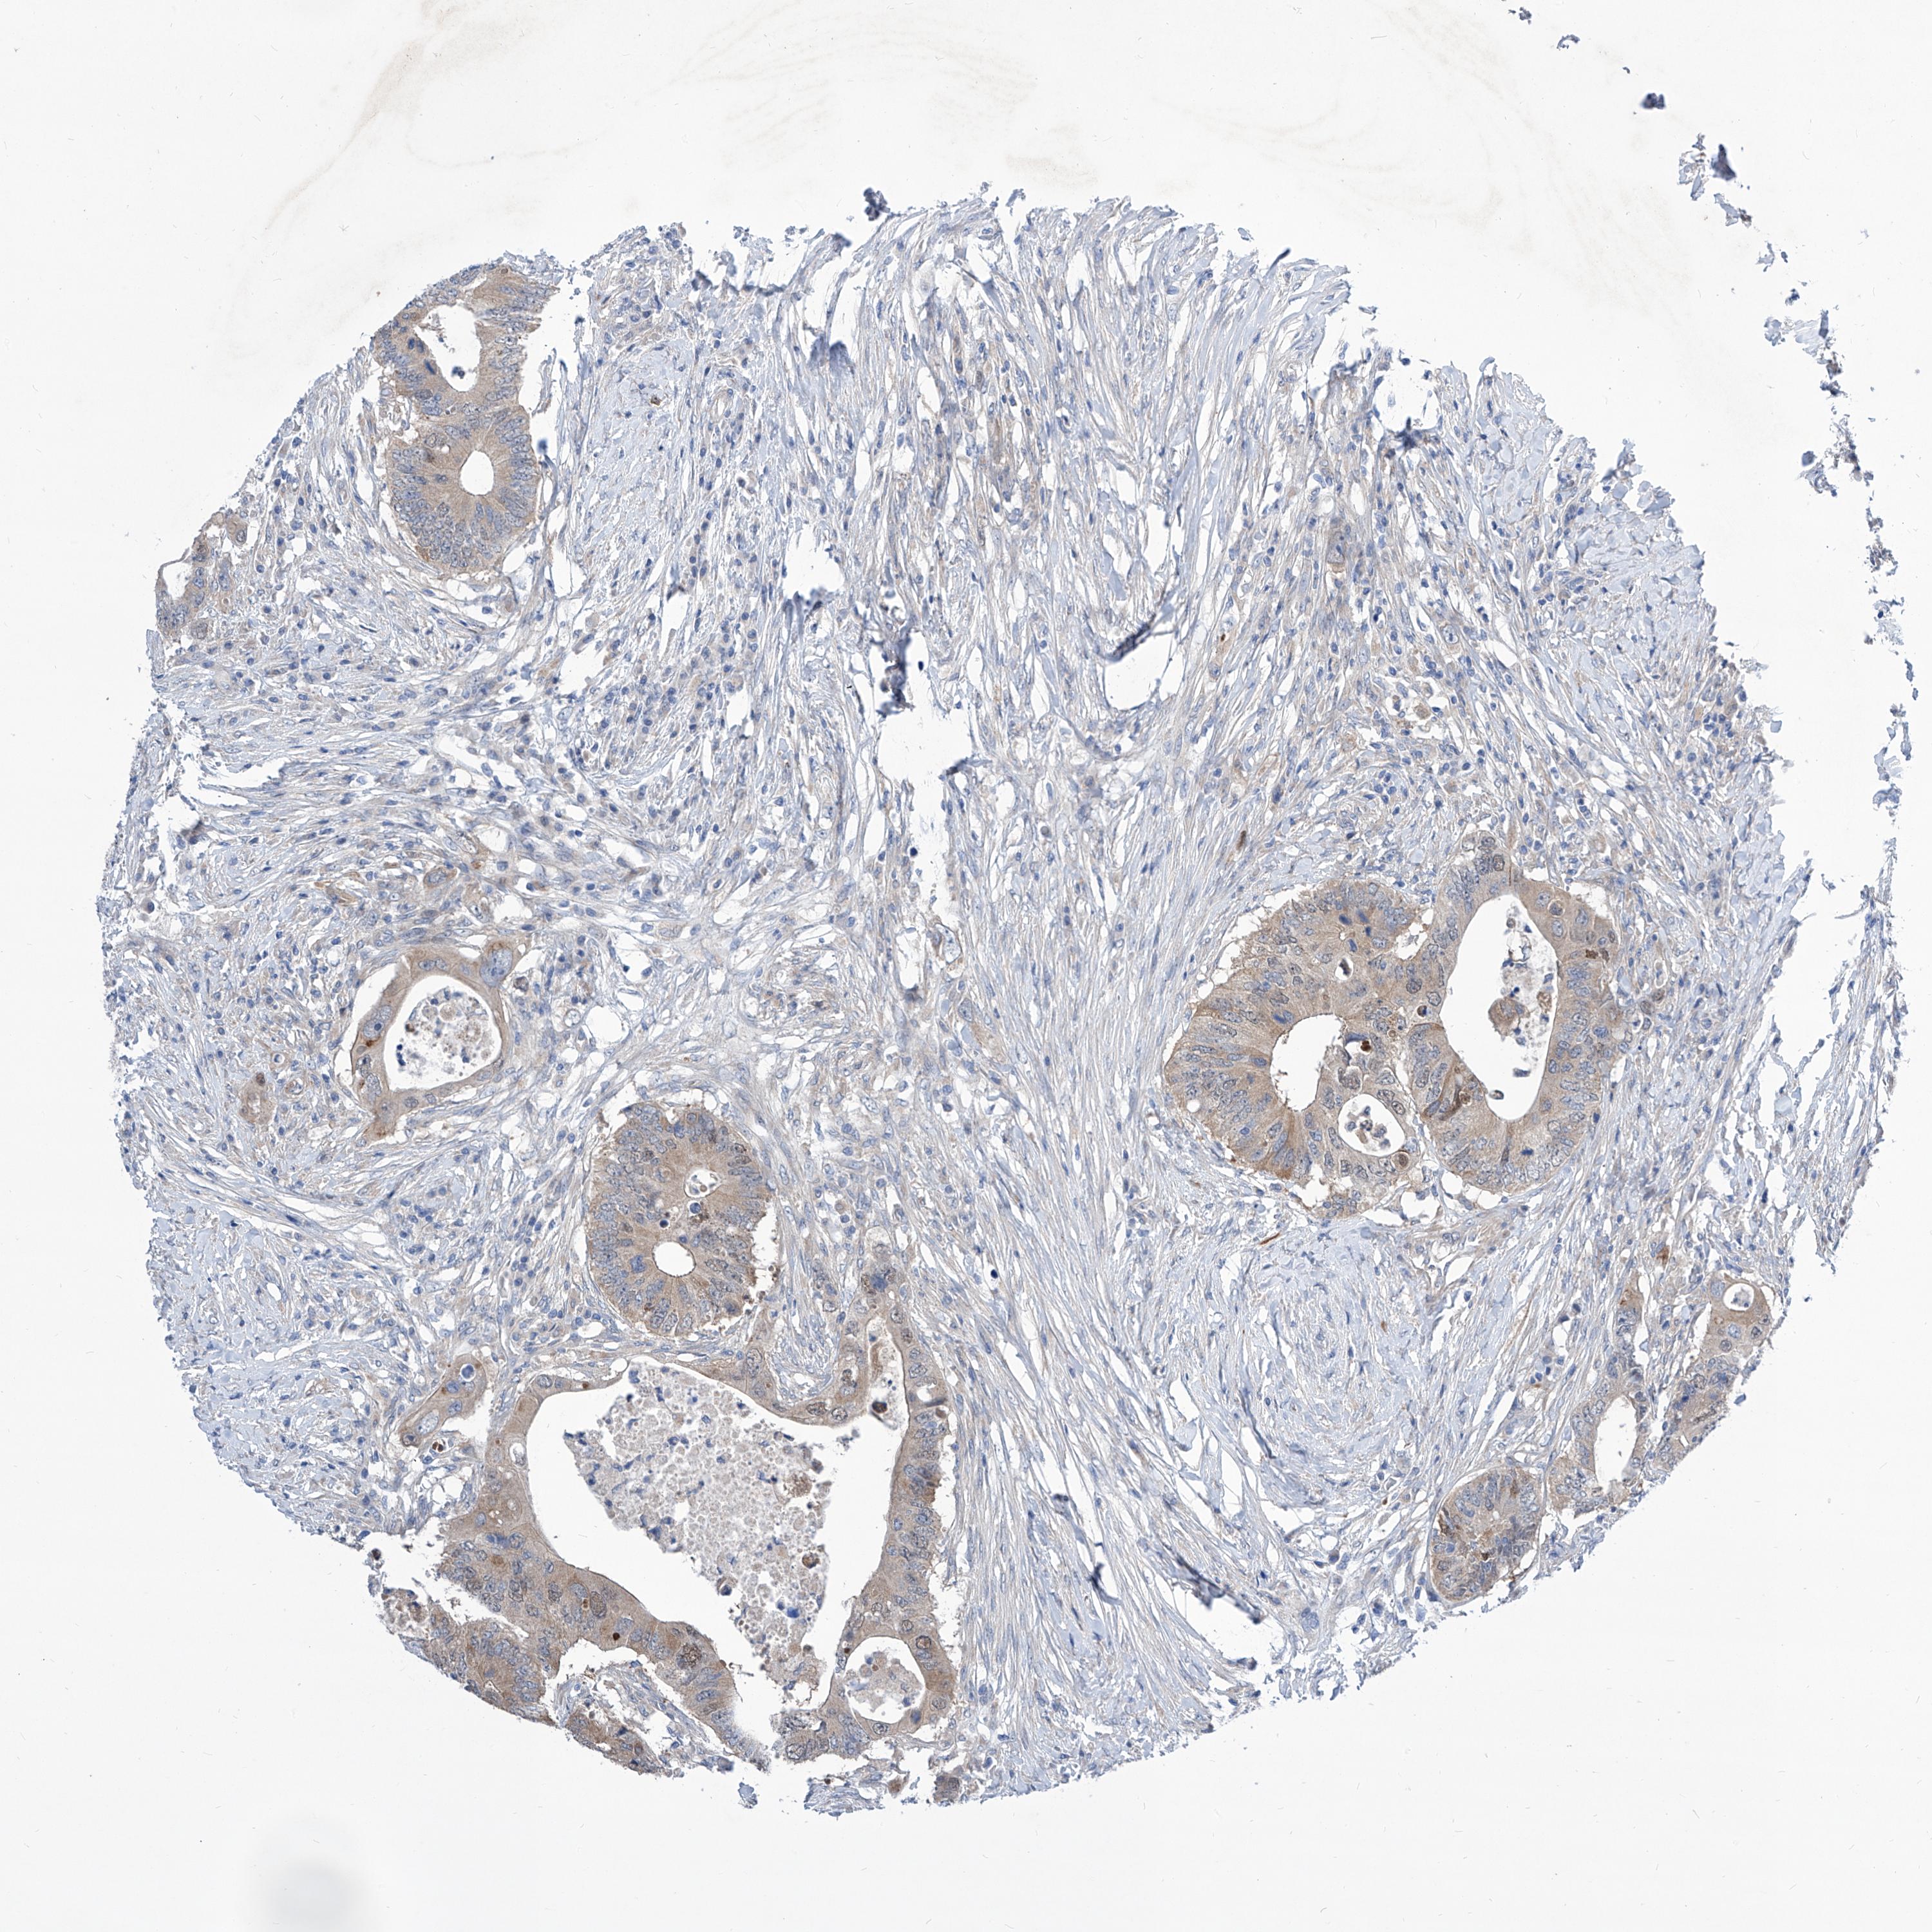

CANCER COLORECTAL CANCER Show tissue menu

Colorectal cancer

Human cancer

Colon adenocarcinoma

COLON ADENOCARCINOMA (TCGA) - Interactive survival scatter ploti

The Survival Scatter plot shows the clinical status (i.e. dead or alive) for all individuals in the patient cohort, based on the same data that underlies the corresponding Kaplan-Meier plots. Patients that are alive at last time for follow-up are shown in blue and patients who have died during the study are shown in red.

The x-axis shows the expression levels (FPKM) of the investigated gene in the tumor tissue at the time of diagnosis. The y-axis shows the follow-up time after diagnosis (years). Both axes are complimented with kernel density curves demonstrating the data density over the axes. The top density plot shows the expression levels (FPKM) distribution among dead (red) and alive patients (blue). The right density plot shows the data density of the survived years of dead patients with high and low expression levels respectively, stratified using the cutoff indicated by the vertical dashed line through the Survival Scatter plot. This cutoff is automatically defined based on the FPKM cutoff that minimizes the p-score. The cutoff can be changed by dragging the vertical line or by entering a cutoff value in the square labeled "Current cut-off".

Under the Survival Scatter plot the p-score landscape (black curve; left axis) is shown together with dead median separation (red curve; right axis). Dead median separation is the difference in median mRNA expression between patients who have died with high and low expression, respectively. It is calculated as follows: median FPKM expression of dead patients with high expression - median FPKM expression of dead patients with low expression. This is intended to aid the user in visually exploring custom cutoffs and the associated p-scores and dead median separation.

Individual patient data is displayed and can be filtered by clicking on one or more of the category buttons on the top of the page. Categories describing expression level and patient information include: high, low, alive, dead, female, male and tumor stages. The scale of the x-axis can be toggled between linear and log-scale by clicking on the "x log" button. Mouse-over function shows TCGA ID, patient information and mRNA expression (FPKM) for each patient.

& Survival analysisi

Kaplan-Meier plots summarize results from analysis of correlation between mRNA expression level and patient survival. Patients were divided based on level of expression into one of the two groups "low" (under cut off) or "high" (over cut off). X-axis shows time for survival (years) and y-axis shows the probability of survival, where 1.0 corresponds to 100 percent.

SRBD1 is not prognostic in Colon Adenocarcinoma (TCGA)

Best expression cut offi

Based on the FPKM value of each gene, patients were classified into two groups and association between prognosis (survival) and gene expression (FPKM) was examined. The best expression cut-off refers the FPKM value that yields maximal difference with regard to survival between the two groups at the lowest log-rank P-value. Best expression cut-off was selected based on survival analysis .

When clicking on this number, the vertical dashed line indicating cut-off, the interactive survival plot, and the Kaplan-Meier curve will be adjusted to show results based on the best expression cut-off.

: 6.92

Median expressioni

Median expression refers to the median FPKM value calculated based on the gene expression (FPKM) data from all patients in this dataset. When clicking on this number, the vertical dashed line indicating cut-off, the interactive survival plot, and the Kaplan-Meier curve will be adjusted to show results based on the median expression.

: N/A

P scorei

Log-rank P value for Kaplan-Meier plot showing results from analysis of correlation between mRNA expression level and patient survival.

N/A

5-year survival highi

5-year survival for patients with higher expression than the expression cutoff.

For melanoma and glioma, 3-year survival is shown.

5-year survival lowi

5-year survival for patients with lower expression than the expression cutoff.

TCGA RNA samplesi

RNA-seq data is reported as average FPKM (number Fragments Per Kilobase of exon per Million reads), generated by the The Cancer Genome Atlas (TCGA) .

Normal distribution across the dataset is visualized with box plots, shown as median and 25th and 75th percentiles. Points are displayed as outliers if they are above or below 1.5 times the interquartile range. FPKM values of the individual samples are presented next to the box plot.

Average pTPM 6.9

Number of samples 254